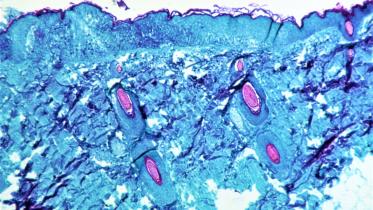

What you need to know about monkeypox

According to the BBC, over 80 cases of monkeypox have been verified in at least 12 countries, including the United States, Canada, Australia, the United Kingdom, Spain, Portugal, Germany, Belgium, France, the Netherlands, Italy, and Sweden recently. The situation is evolving and the World Health Organisation (WHO) expects there will be more cases of monkeypox identified as surveillance expands in non-endemic countries. Immediate actions focus on informing those who may be most at risk for monkeypox infection with accurate information, in order to stop further spread.